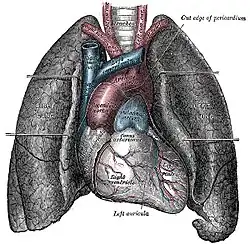

Disposición de los pulmones en el tórax, en el centro el corazón y los grandes vasos. | ||

Circulación

El pulmón recibe la sangre procedente del ventrículo derecho a través de la arteria pulmonar. La arteria pulmonar se divide en dos ramas una para el pulmón derecho y otra para el izquierdo, las cuales se ramifican progresivamente siguiendo un trayecto paralelo al de las vías respiratorias. El sistema venoso es más variable y puede disponerse en diferentes trayectos, pero finalmente las cuatro venas pulmonares, dos procedentes del pulmón derecho y dos del izquierdo, desembocan en la aurícula izquierda. Hay que tener en cuenta que la circulación pulmonar presenta una peculiaridad con respecto al resto de la circulación sistémica, puesto que las arterias pulmonares son las únicas arterias del organismo que transportan sangre desoxigenada, mientras que las venas pulmonares, tras el intercambio gaseoso en los alvéolos, aportan sangre oxigenada hacia la aurícula izquierda, el intercambio entre oxígeno y dióxido de carbono se realiza mediante difusión entre la luz de los alveolos pulmonares y los capilares sanguíneos.[4]

Por otra parte el pulmón recibe sangre oxigenada a través de las arterias bronquiales que surgen directamente de la arteria aorta, esta sangre oxigenada irriga sobre todo las paredes de los bronquios y los bronquiolos.[4]